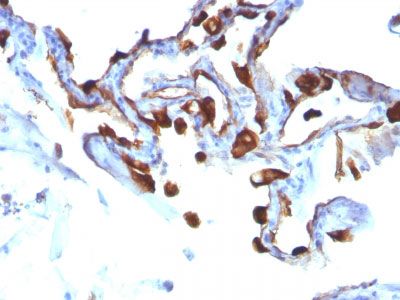

Formalin-fixed, paraffin-embedded human Lung Carcinoma stained with Cytokeratin 8 Monoclonal Antibody (KRT8/803). |